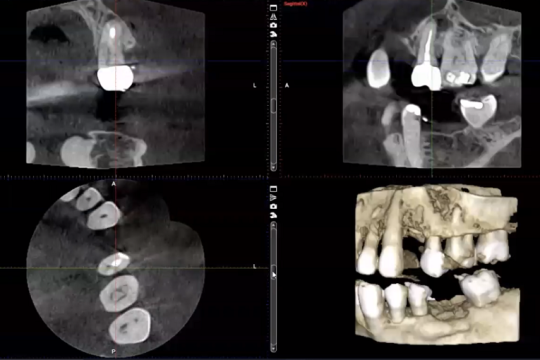

3D Dentistry Roadmap: Paradigm Shift Ahead

This webinar will explore both 2D and 3D imaging, and look at whether it is time for a paradigm shift in how we use this...